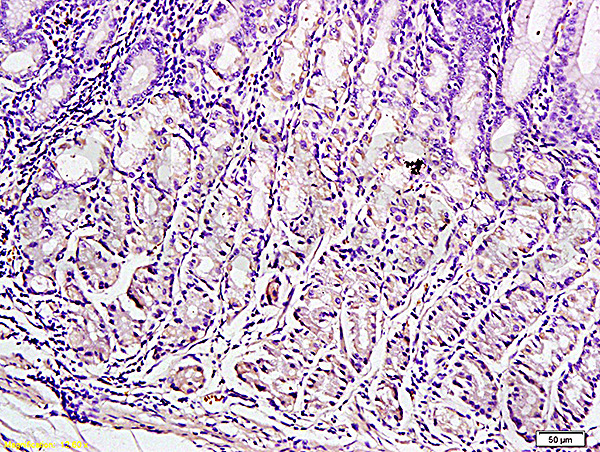

- Main image

- Experimental details

- Formalin-fixed and paraffin embedded human gastric tissue labeled with Anti-Leptin Polyclonal Antibody (bs-0409R), Unconjugated at 1:300, followed by conjugation to the secondary antibody and DAB staining

- Sample type

- Human

- Other comments

- Stomach